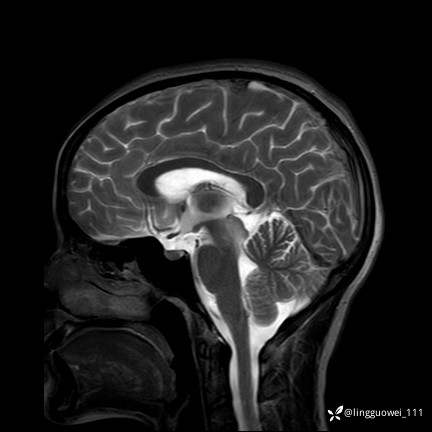

T2

img